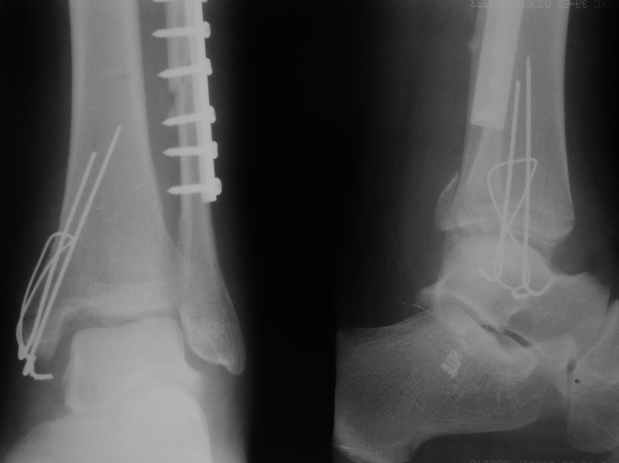

>На сделанных у нас снимках видно, что не все благополучно...

Неравномерность суставной щели может быть связана с разрывом глубокой порции дельтовидной связки и ротацией м/берцовой кости за счет поврежденных структур синдесмоза(репозиция ее на уровне перелома как-будто удовлетворительная).

Мы бы, сблизив берцовые кости чрескожно наложенным репозиционным зажимом, провели позиционный межберцовый винт чуть ниже пластинки в положениий максимального тального сгибания стопы и ... на следующий день разрешили бы полностью наступать без гипса, брейса и т.п., но в обуви с небольшим каблуком 2-3 см и супинатором. Через месяц-полтора -винт удалить (если конечно не сломается).

По моему мнению,ассиметрия суставной щели обусловлена импрессией медиальной части суставной поверхности б/б кости. Да, позиционный винт здесь не лишен, но через 4 недели целесообразность его проведения сомнительна, брейс, ограничение осевой нагрузки достаточно.Есть еще деонтологические аспекты повторной операции, не все так плохо выполнено предыдущим доктором!

Импрессия медиальной части суставной поверхности бывает при супинационном механизме перелома лодыжек (тип А по классификации АО). Здесь механизм пронациия+наружная ротация (тип С, синдесмоз и межкостная мебрана повреждены),

перелом медиальной лодыжки отрывной, при этом в 20-30% бывает повреждение дельтовидной связки.

Выполнено действительно неплохо, только позиционный винт забыли провести.

Клиновидность щели сустава следствие повреждения дельты, невосстановления длины малоберцовой или (хотел сказать "установки в гипсе", но оного, вроде,

нет)? Устранить бы причину. А равно как и тенденцию" к наружному подвывиху. Чрескостный остеосинтез - метод выбора.

Мое мнение, что никакой ротации малоберцовой кости здесь нет и синдесмоз тоже впорядке. Все дело в некачественно репозиции медиального мыщелка. Скорее всего его или немного ротировали при операции или сместили латерально. Более склонен ко второму варианту.

Перелом типа Вебер С с эверсионным механизмом травмы всегда сопровождается повреждением дистального межберцового синдезмоза, поэтому вместе с фиксацией переломов лодыжек( малоберцовой кости) автоматом выполняется фиксация синдесмоза винтом, который обычно удаляется через 8 недель -

перед началом полной нагрузки на ногу.

При реконструкции голеностопа, о важности восстановления длины малоберцовой для профилактики пост травматического артроза разбирали в предыдущих дискуссиях. Нарушенную биомеханику голеностопа без восстановления длины малоберцовой, не восстановить только швом медиальной связки.

Расширенная медиальная щель более чем на 4 мм и укорочение малоберцовой более чем 2 мм, а перелом заднего края большеберцовой смещения более 2мм с вовлечением 30% поверхности сустава, считается отходом от нормы голеностопного сустава, и подлежит к оперативному вмещательству.

С мнением «провести позиционный межберцовый винт чуть ниже пластинки в положениий тыльного сгибания стопы» согласен, но я бы нагрузку начал через три недели и удаление шурупа можно провести через 6-8 недель.